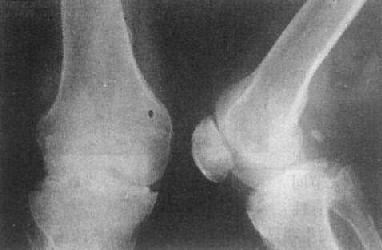

(二)关节破坏 关节破坏(destruction of joint)是关节软骨及其下方的骨性关节面骨质为病理组织所侵犯、代替所致。其X线表现是当破坏只累及关节软骨时,仅见关节间隙变窄,在累及关节面骨质时,则出现相应区的骨破坏和缺损(图2-1-14)。关节间隙变窄和骨破坏程度不同。严重时可引起关节半脱位和变形。

关节破坏是诊断关节疾病的重要依据。破坏的部位与进程因疾病而异。急性化脓性关节炎,软骨破坏开始于关节持重面或从关节边缘侵及软骨下骨质,软骨与骨破坏范围有时十分广泛。关节滑膜结核,软骨破坏开始于边缘,逐渐累及骨质,表现为边缘部分的虫蚀状破坏。类风湿性关节炎到晚期才引起关节破坏,也从边缘开始,多呈小囊状。

图2-1-14 关节破坏——膝关节结核

膝关节关节间隙变窄,关节面边缘有虫蚀状骨破坏